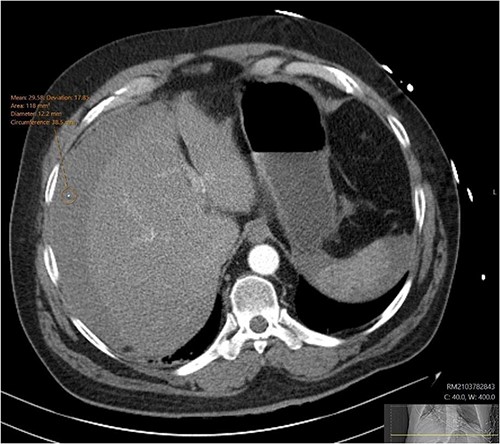

A CT abdomen-pelvis (CT-AP) revealed an acute haematoma inferolateral to the third part of the duodenum and another at the root of the mesentery. High density fluid related to the mesenteric bleed was also seen extending from the right para-colic gutter into the pelvis and in the peri-hepatic region. The patient was admitted under general surgery, stabilized with intra-venous fluid resuscitation, co-amoxiclav and metronidazole and cross matched for four units of blood. A CT-angiogram demonstrated acute haemorrhage throughout the abdomen with a 104 x 62 mm haematoma arising centrally at the level of L2 within the mesenteric fat (Fig. 1). The haematoma did not appear to originate from any specific mesenteric vessels but was related to some mid and distal jejunal loops. The angiogram also showed discontinuity when tracing the proximal and mid jejunal loops inferiorly, extensive haemorrhagic peritoneal fluid around the liver extending inferiorly (Fig. 2) and a small amount of peri-splenic haemorrhagic fluid. Curved reformatting of the angiogram revealed no abnormalities within the superior mesenteric artery (Fig. 3).

Curved reprogramming of the initial CT angiogram. Curved reprogramming of the patient’s initial CT angiogram showed no evidence of an aneurysm within the superior mesenteric artery, effectively ruling this out as a cause of the patient’s acute bleed.